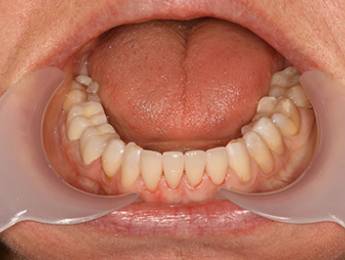

5. eset

Ennek a kedves hölgynek 20 éves álmát váltottuk valóra. 20 évig hordott kivehető fogsorokat. 12 implantátum beültetése után alsó és felső fixen rögzített hidakat készítettünk. Nincs többé kivehető - evéskor, beszéd közben - elmozduló fogsor. Javult a rágási hatékonyság is, amely az egészséges táplálkozás szempontjából is nagyon fontos tényező.